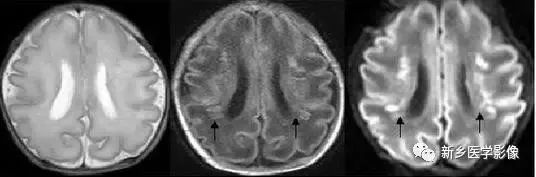

❺ 脑室周围白质软化症

主要与缺血缺氧及感染有关。常见于早产儿,是造成早产儿脑瘫的主要原因。

由于脑室周围白质的血供分别来自脑室区和远脑室区的终动脉,未成熟儿终动脉深穿支的侧支循环尚未建立,而胚胎晚期脑室周围白质对缺血缺氧敏感,所以,脑室周围自质软化症多见于早产儿。

由于病灶常为双侧性,故双侧侧脑室多同时扩大。脑白质内软化灶在CT扫描时表现为白质内斑片状低密度灶,MR上T1加权图呈低信号,T2加权图呈高信号。

❻ 脑室周围白质软化症

主要与缺血缺氧及感染有关。

常见于早产儿。原因与胚胎期脑部损害发生的时间有关:胚胎早中期脑损害主要引发发育畸形,晚期主要引起脑血管改变。

由于侧脑室周围有软化萎缩,故扩大的侧脑室外缘常不规则、不光整,这种不规则、不光整是本病引起脑室扩大的特。另外,本病均表现有脑白质量减少及脑白质内斑片状软化病灶,脑白质减少严重时表现为部分区域白质消失,脑皮层与脑室侧缘接近甚至相连。CT表现为斑片状低密度灶。MR T1WI上呈低信号,T2WI呈高信号。